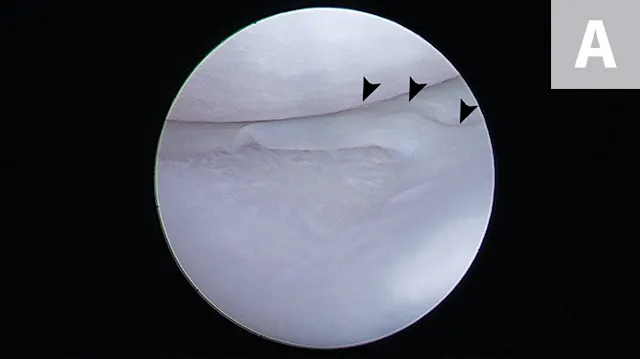

FIGURE 4A

Arthroscopic images showing a small bucket handle tear in the caudal pole of the medial meniscus (A; arrowheads). The meniscus is palpated with a meniscal probe (B; P). The torn portion of meniscus is removed with an arthroscopic shaver (C; S). After removal of the diseased meniscus, the remaining outer rim of the meniscus is left intact (D).